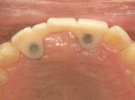

47歳女性

ブリッジや義歯でも可能な症例ですが、残っている歯を守りたいという患者さんの希望によりインプラント施術。

なお、この患者さんは歯医者の方で、専門知識の高い歯科医師の方にも喜んでもらえて大変光栄でした

術前

↓↓↓↓

術後